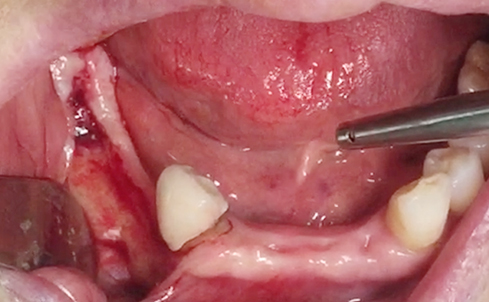

Implants/Bone Grafting

Partial edentulous clinical cases